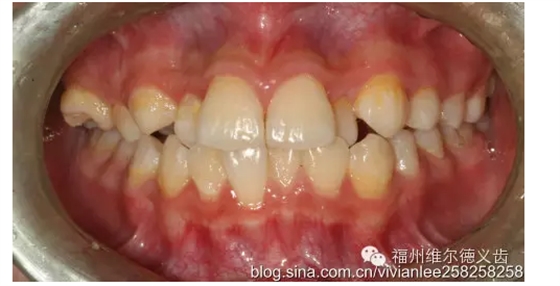

牙周角度來說同樣,每年洗牙的話,洗牙費用在1-5百不等,沒有做,好,最后牙周病,骨頭吸收,單純洗牙不好使了,需要牙周刮治,得三五千的進去了,還不好好清潔、炎癥得不到控制的話,得反復(fù)刮,動不動三五千,甚至需要牙周手術(shù)、植骨,一顆好幾千...

乳牙更是了,本來礦化度就低,相對恒牙來說更容易壞,涂氟、窩溝封閉沒做,最后乳牙壞了,你說沒事,乳牙反正要換,但是你造嘛,乳牙齲壞直接影響恒牙生長,最常見的影響是,恒牙長歪了,好吧,這回需要做矯正,矯正的費用那可就是好幾萬了。